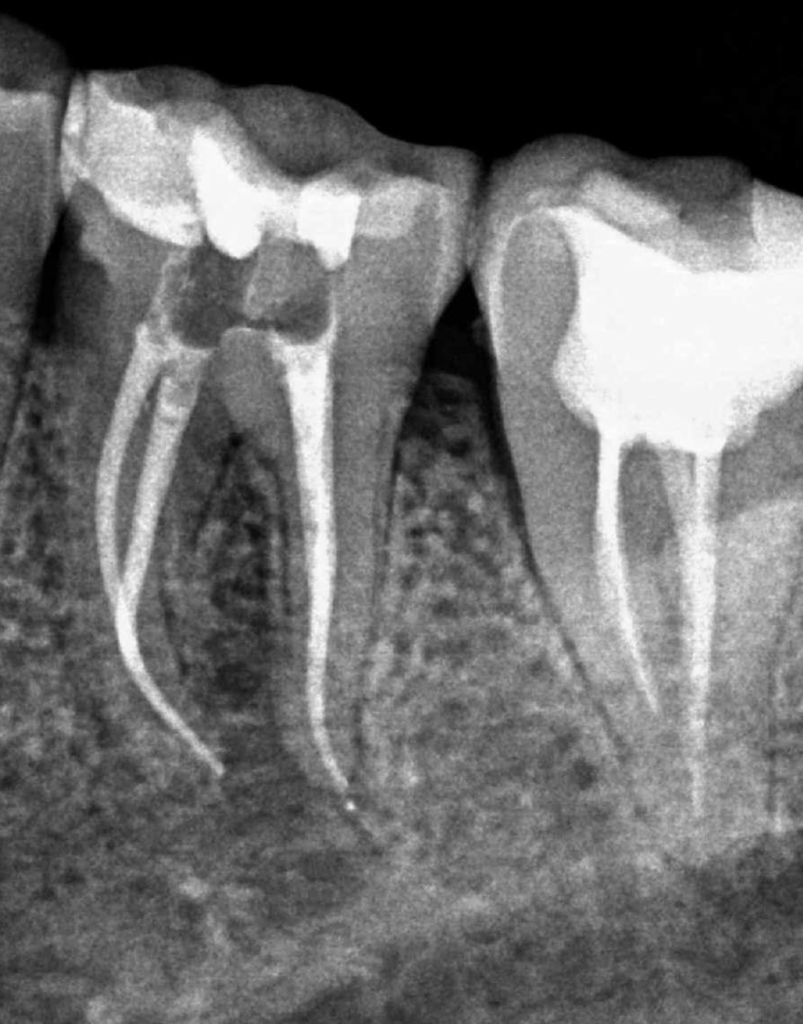

Fisura, remoción amalgama para explorar